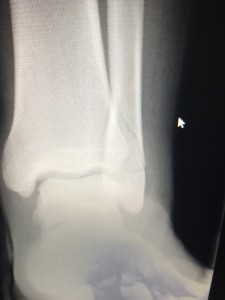

先々月の末に骨折😅

見事な腓骨骨折💦💦

こーんなに腫れて、内出血もしてたけど、

回復力がハンパなく、

3月下旬ギプスを外し、

無事、九州に旅立っていきました✨